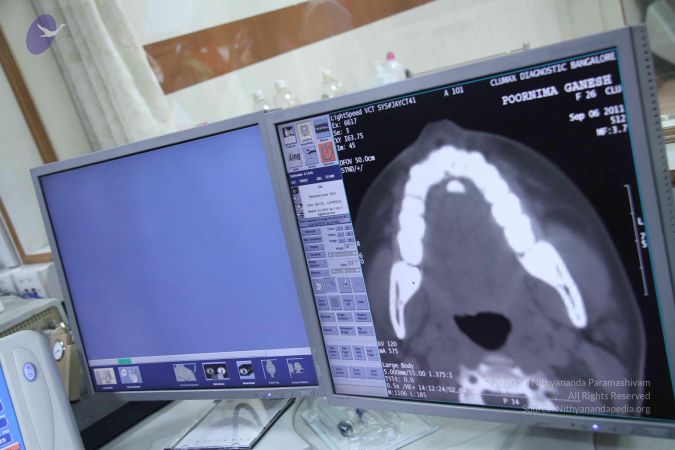

Scientific Validation of Materialization The most significant in a series of studies conducted by the research team were the tests done on Poornima (Ma Nithya Mahayogananda), a young entrepreneur and Paramahamsa Nithyananda’s energy channel from Singapore. On 6th September 2011, three different studies were conducted during a 4-hour session, in which Paramahamsa Nithyananda materialized a variety of objects through this individual, including sacred ash and precious stones. The studies were: 1) Whole body baseline CT scan of the subject Baseline whole-body CT scans proved the absence of any hidden objects in the body and vicinity of the subject. After the energy transfer from Paramahamsa Nithyananda to the subject, a repeat scan clearly shows the sudden appearance of a radio-opaque foreign body in the oral cavity without any delay or repositioning. The recording of the spiral CT after materialization revealed the presence of materialized objects both in sections and 3D format. 2) Simultaneous qEEG of Paramahamsa Nithyananda and the subject The qEEG recording of both Paramahamsa Nithyananda and the subject done during the process of energy transfer clearly showed ‘Entrainment’ (Synchronicity) in the brain waves of both individuals during the process of materialization, proving that a process of attunement was indeed taking place at the time

CT-SCAN-STUDIES-TO-DOCUMENT-POWER-OF-MATERIALISATIONIN-DEVOTEE-UNDER-CONTROLLED-CONDITIONS-PRE-AND-POST-INITIATION-BY-HDH